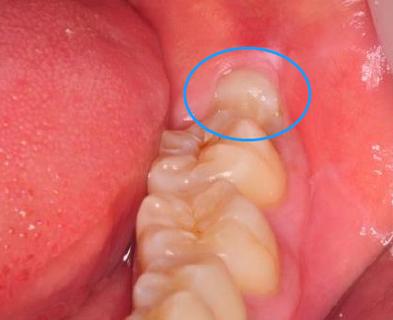

智齿的“晚长”不仅仅是时间上的问题,它还可能带来一系列潜在的口腔健康问题。最常见的就是智齿位置不正,导致部分牙齿生长不完全,甚至出现牙龈肿胀、疼痛等症状。智齿如果长得过晚,可能会与相邻的牙齿产生冲突,甚至对其他牙齿造成挤压,增加了牙齿拥挤的风险。

智齿如果萌出得过晚,也可能没有足够的空间生长,导致“阻生智齿”的情况。阻生智齿是指牙齿因为空间不足而无法正常萌出,通常需要通过手术去除。阻生智齿常常伴随着感染、炎症和持续的疼痛,给患者带来巨大的困扰。

如果你发现智齿长得歪斜,或者出现持续性的疼痛、牙龈肿胀等问题,最好咨询口腔医生是否需要拔除智齿。拔除智齿的时机通常是在其未完全萌出之前,这样手术相对简单,恢复也较为迅速。